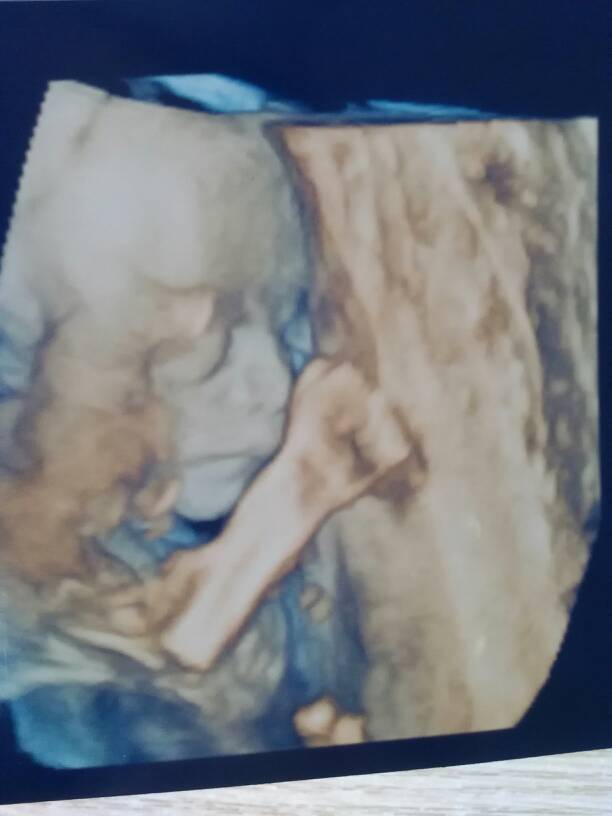

四维通过了,今天怀孕22周哦,宝宝很健康宝妈们看看我家宝宝长的怎么样??? 四维通过了,今天怀孕22周哦,宝宝很健康宝妈们看看我家宝宝长的怎么样??? 点击展开 素颜520 2015-07-04 12:58 为您推荐: 其他回答 萌萌哒,, 嘛嘛爱小宝 2015-07-04 13:22 长的挺漂亮的 人苼、偌呮如初 2015-07-04 13:21 宝妈好孕啊 137*****348_1Td5 2015-07-04 13:21 一定是个大高个 涵涵的娘亲 2015-07-04 13:15 祝好孕,, 鸡仔家族 2015-07-04 13:14 加载更多 相关问题 请问,怀孕6个月的时候做四维是看宝宝的健康吗?? 宝妈,帮忙看看我照的四维的是男孩还是女孩 看看我宝的四维,像男孩还是女孩啊